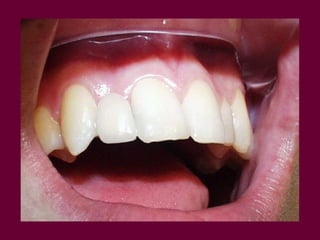

Conocer los diversos recursosprotéticos que dispone la odontología Prótesis fija Prótesis removible parcial Prótesis removible total Prótesis implanto-asistida